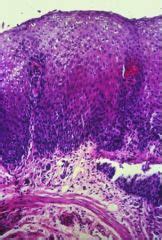

Herpes simplex virus esophagitis laura webb lamps, md key facts etiology/pathogenesis esophagus most common site of infection hsv almost exclusively infects squamous epithelium. Causes of esophagitis include stomach acids backing up into the esophagus, infection, oral medications and allergies. Gout pathology ulcerative colitis pathology. May cause esophageal perforation or. Esophagitis can occur from irritation from toxic or abrasive materials ingested or from gastric reflux. Peritoneum and peritoneal cavity disorders. Hiv (idiopathic) esophagitis may be the cause if no other pathogens are. Eosinophilic esophagitis attributed to gastroesophageal re. This condition occurs in the setting of patients with a weakened immune system who are susceptible. Herpes esophagitis is a viral infection of the esophagus caused by herpes simplex virus (hsv). Herpes esophagitis is an inflammation of the esophagus due to herpes simplex virus. Occurs with patients who have oral lesions reflux esophagitis 1. The latter can occur frequently during anesthesia or deep sedation.

Pathology of Herpes Simplex Virus Infection - Dr Sampurna ... from www.histopathology-india.net Herpes simplex virus (hsv) is a common cause of infectious esophagitis. Self limited in healthy patients; Herpes esophagitis is one of the infectious esophagitis that usually affects immunocompromised patients. This page contains notes on herpes simplex viruses. Epidemiology it occurs as an opportunistic infection in immunocompromised patients. Esophagitis is the inflammation or irritation of the esophagus. #2 most common cause of infectious esophagitis after candida. The majority of patients with eosinophilic esophagitis have a personal history of allergic disorders such as.